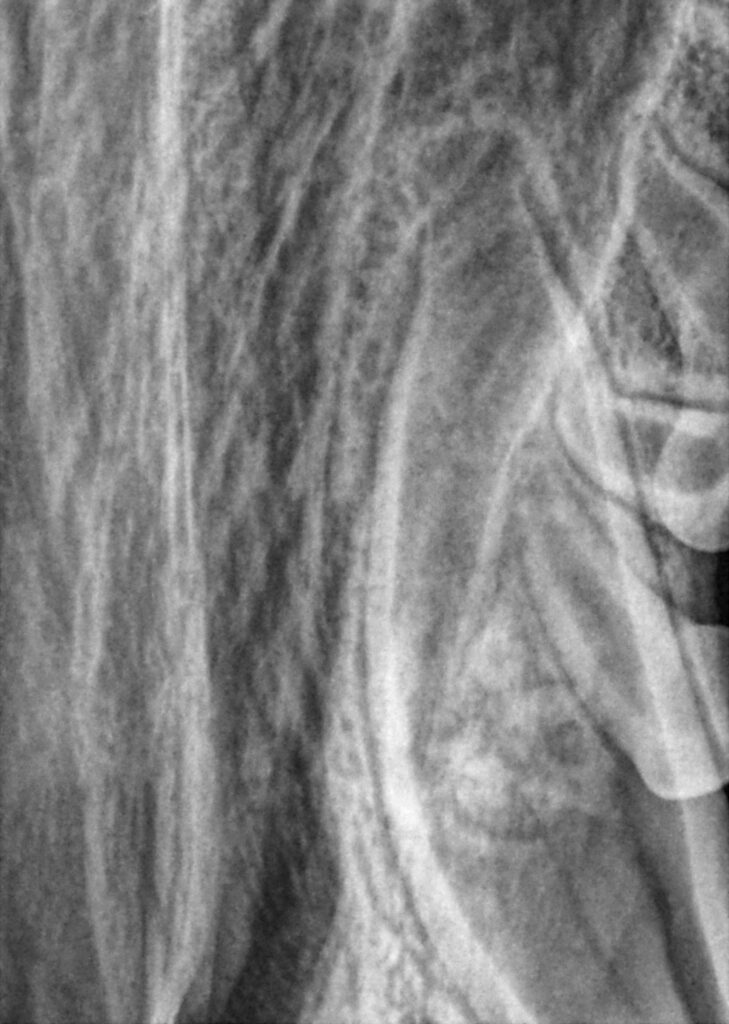

A 6.5-month-old standard poodle was presented to VDS for a fracture of the maxillary left canine (204). (Figures 1a-1c)

Normally, fractured teeth can have a very good prognosis; however, two issues complicated the procedure in this case. First, there was a deep subgingival fracture on the tooth. This extended below the bone, which will create periodontal issues. In addition, because the patient was so young, the root was not complete (Figure 2), and thus standard root canal therapy was not an option.